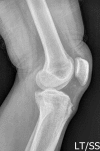

Figure 2. Separated ossicle and bony prominence seen in lateral radiography of knee in OSD.